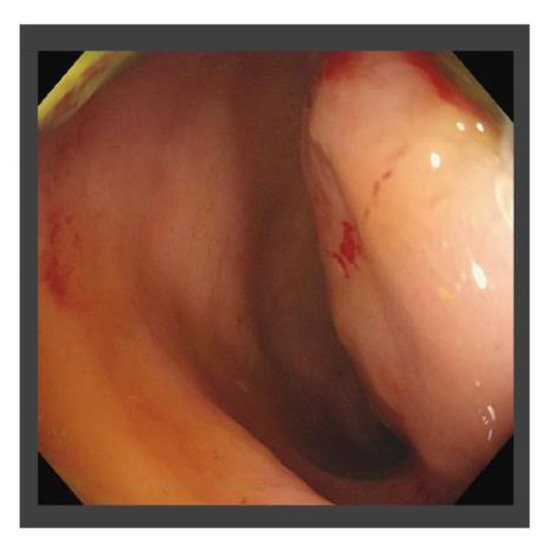

| X + 1 | July | Occasional bloody stool and the diagnosis of radiation proctitis (grade 1) by colonoscopy |